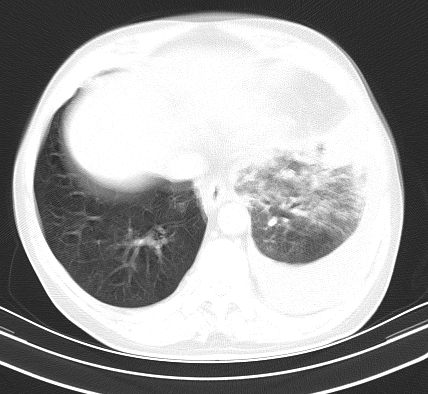

以下是引用老爱克斯新网客在2008-7-31 6:30:00的发言:[br]左肺上叶大片状病灶,左肺上叶支气管狭窄呈鼠尾状,左肺门增大,纵隔内见肿大淋巴结,左侧胸腔积液,余肺清晰。左肺中心型肺癌淋巴结转移,

以下是引用zjb在2008-7-31 6:32:00的发言:[br]左侧中心性肺癌 阻塞性肺炎 肺不张 胸腔积液 建议气管镜

以下是引用zjzjr在2008-7-31 8:45:00的发言:[br]考虑左侧中心性肺癌伴阻塞性肺炎,左肺上叶肺不张,纵隔淋巴结转移;左侧胸腔积液。建议行纤支镜检查。

以下是引用sdzyy在2008-7-31 8:47:00的发言:[br]病灶较治疗前有所进展,胸水增多, 左侧中心性肺癌 并 阻塞性肺炎 肺不张 胸腔积液 可能性大; 建议气管镜检查。 [br] [br]